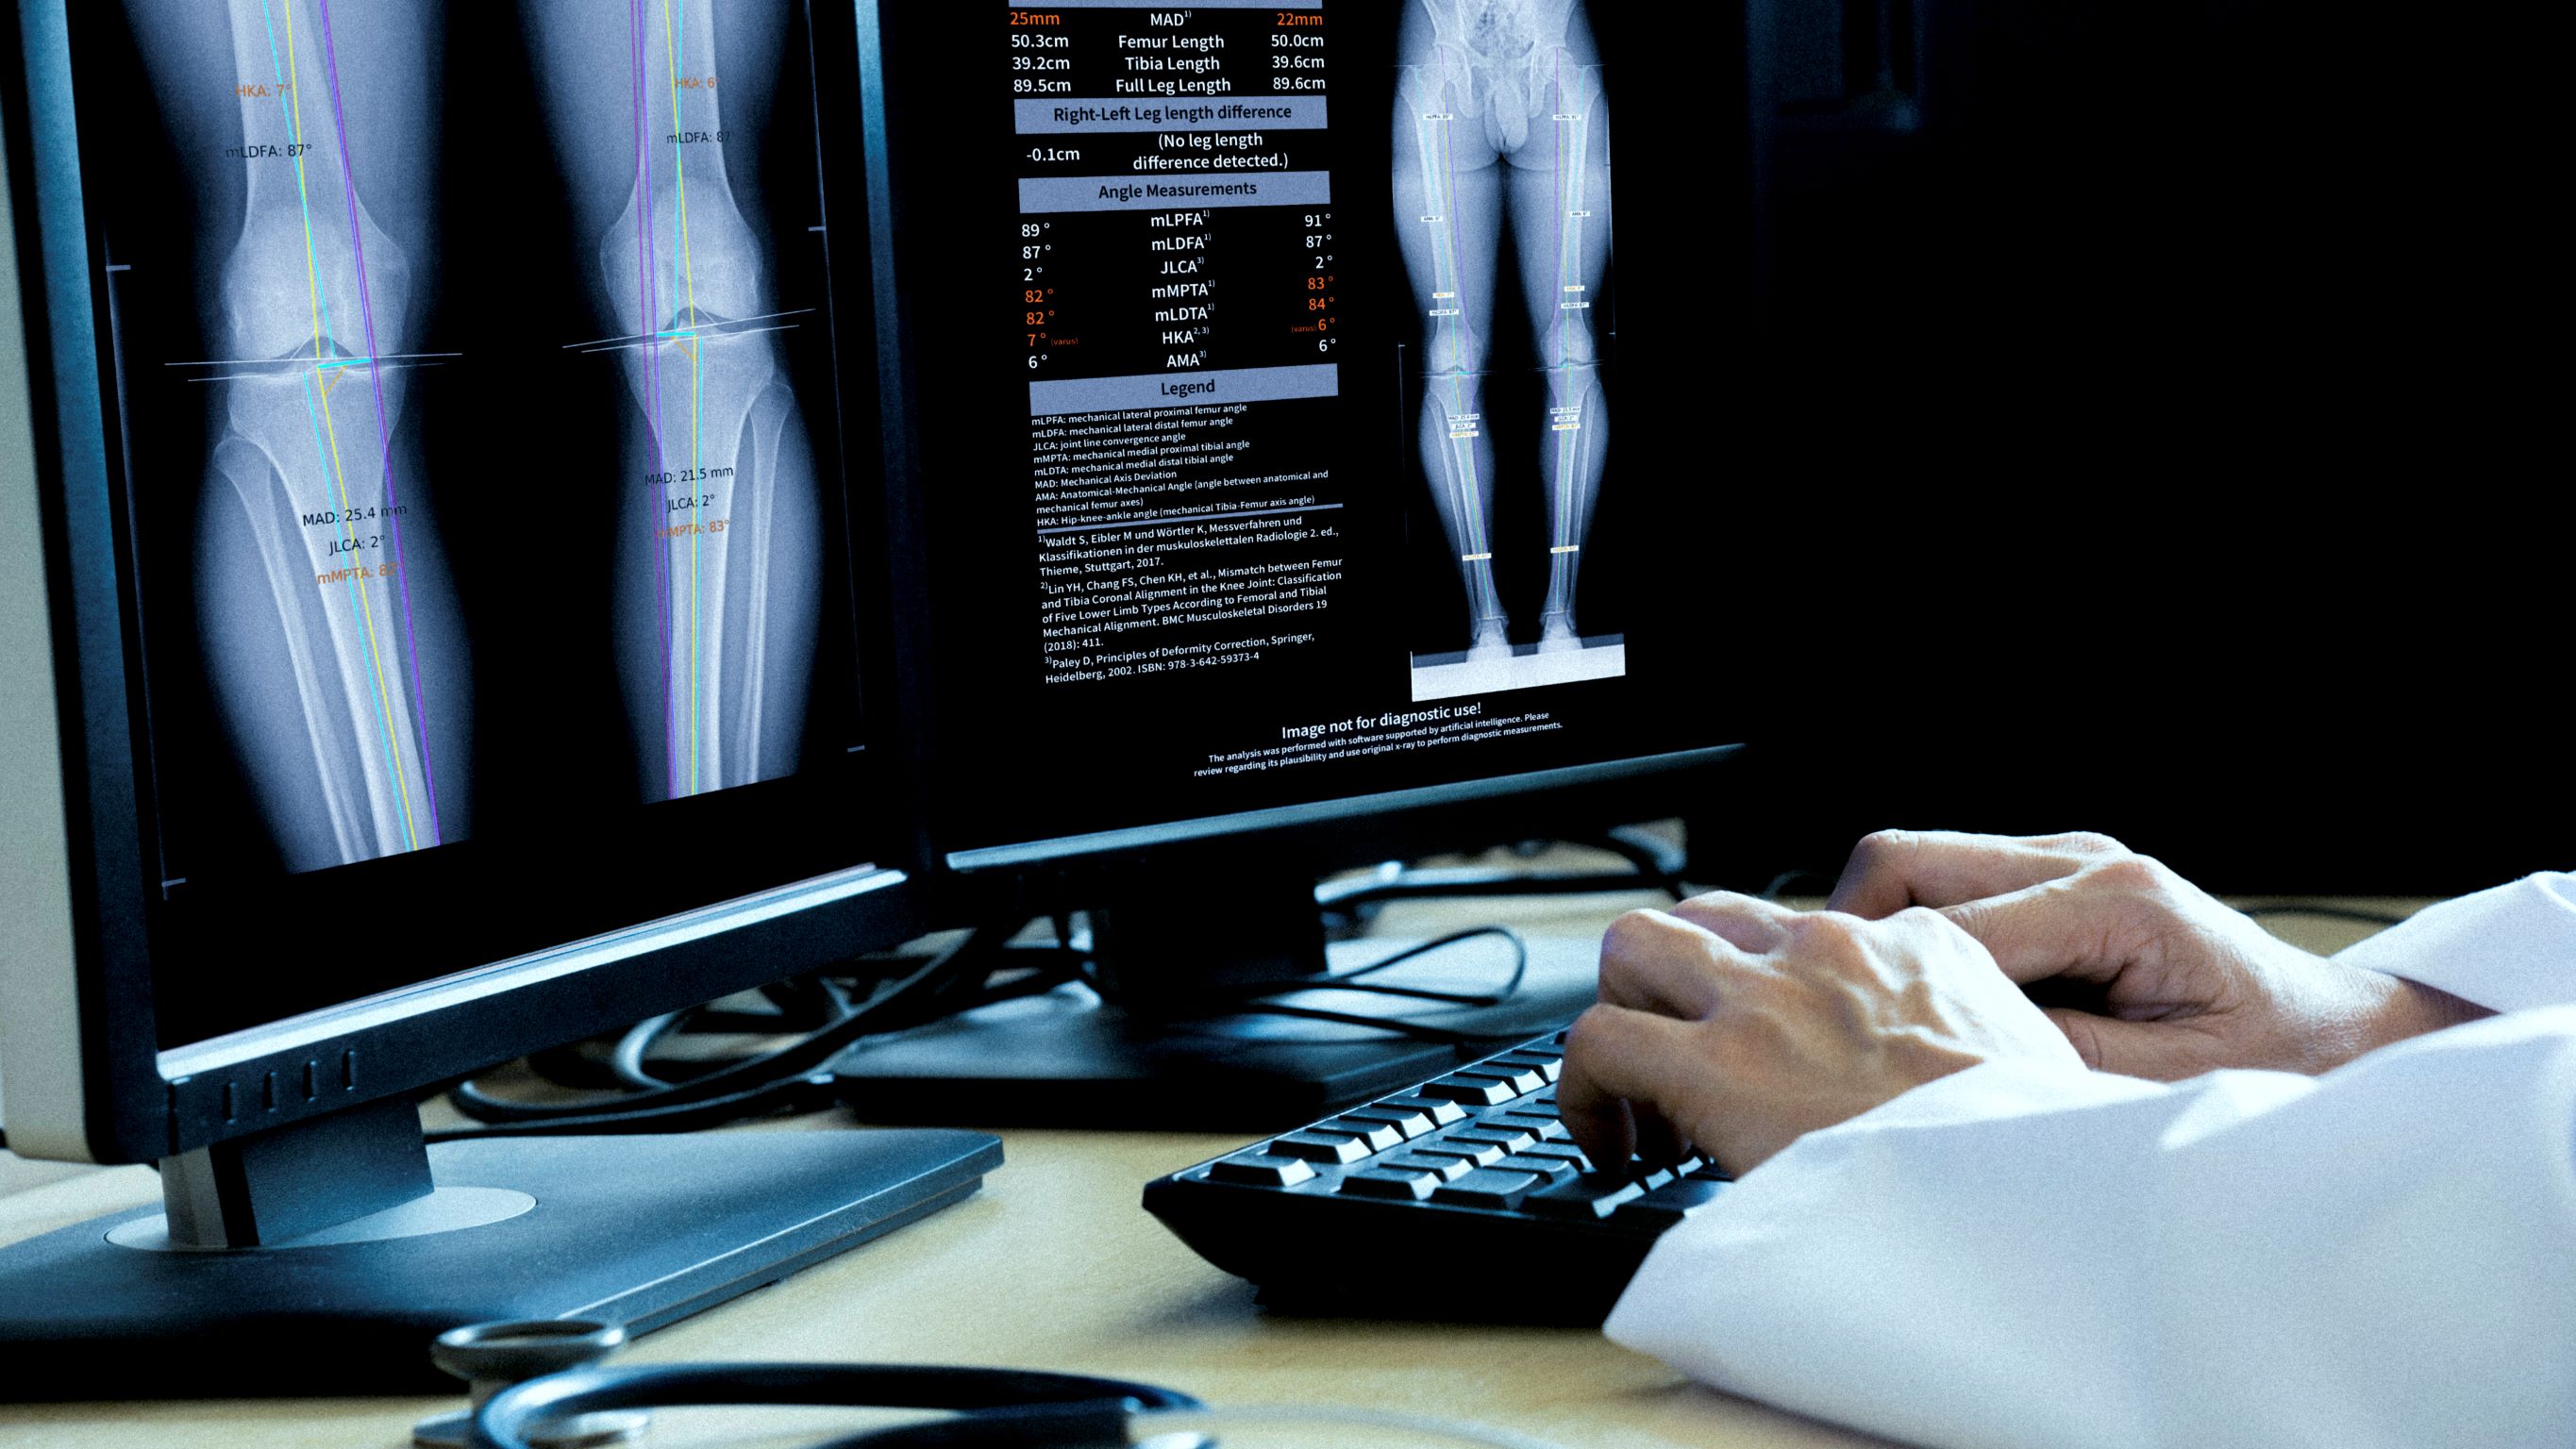

IB Lab LAMA is one of four MSK modules that provide diagnostic support for the most common bone and joint diseases in medical practices and clinics. The application was developed for MSK-radiologists and orthopedic surgeons, providing up to twelve measurements on long-leg X-rays with or without hip or knee implants. IB Lab LAMA automatically locates the anatomical features of the femur, tibia, and calibration ball to provide all the landmarks needed for the required measurements. If a calibration ball is available, IB Lab LAMA uses a corresponding magnification factor for the length measurement.